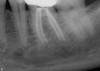

Excellent diagnosis essentially begins with two fundamental components: a doctor willing to listen to the patient’s chief complaint, and proper diagnostic tools. Among the most important tools are a precise periapical radiograph (PA) and bitewing (BW). Although a PA is often enough to provide an accurate portrayal of the patient’s condition, sometimes it alone does not suffice. Figure 1, Figure 2, and Figure 3 demonstrate a case that illustrates this point clearly. Despite two acceptable PAs (Figure 1 and Figure 2), it is difficult to assess the source of the patient’s pain to temperature. However, the BW radiograph Figure 3 provides significantly more clarity than either of the two PAs. The BW depicts localized bone loss (around tooth No. 2), a pulp stone (No. 2), a flat occlusion, numerous calcified canals, multiple restorations in tooth No. 30, and gross decay especially on tooth No. 3, which is the source of the patient’s pain to temperature. In this instance these images depict how much more useful a BW can be than just a conventional PA.

Fig 1. Foreshortened PA radiograph.

Figure 1